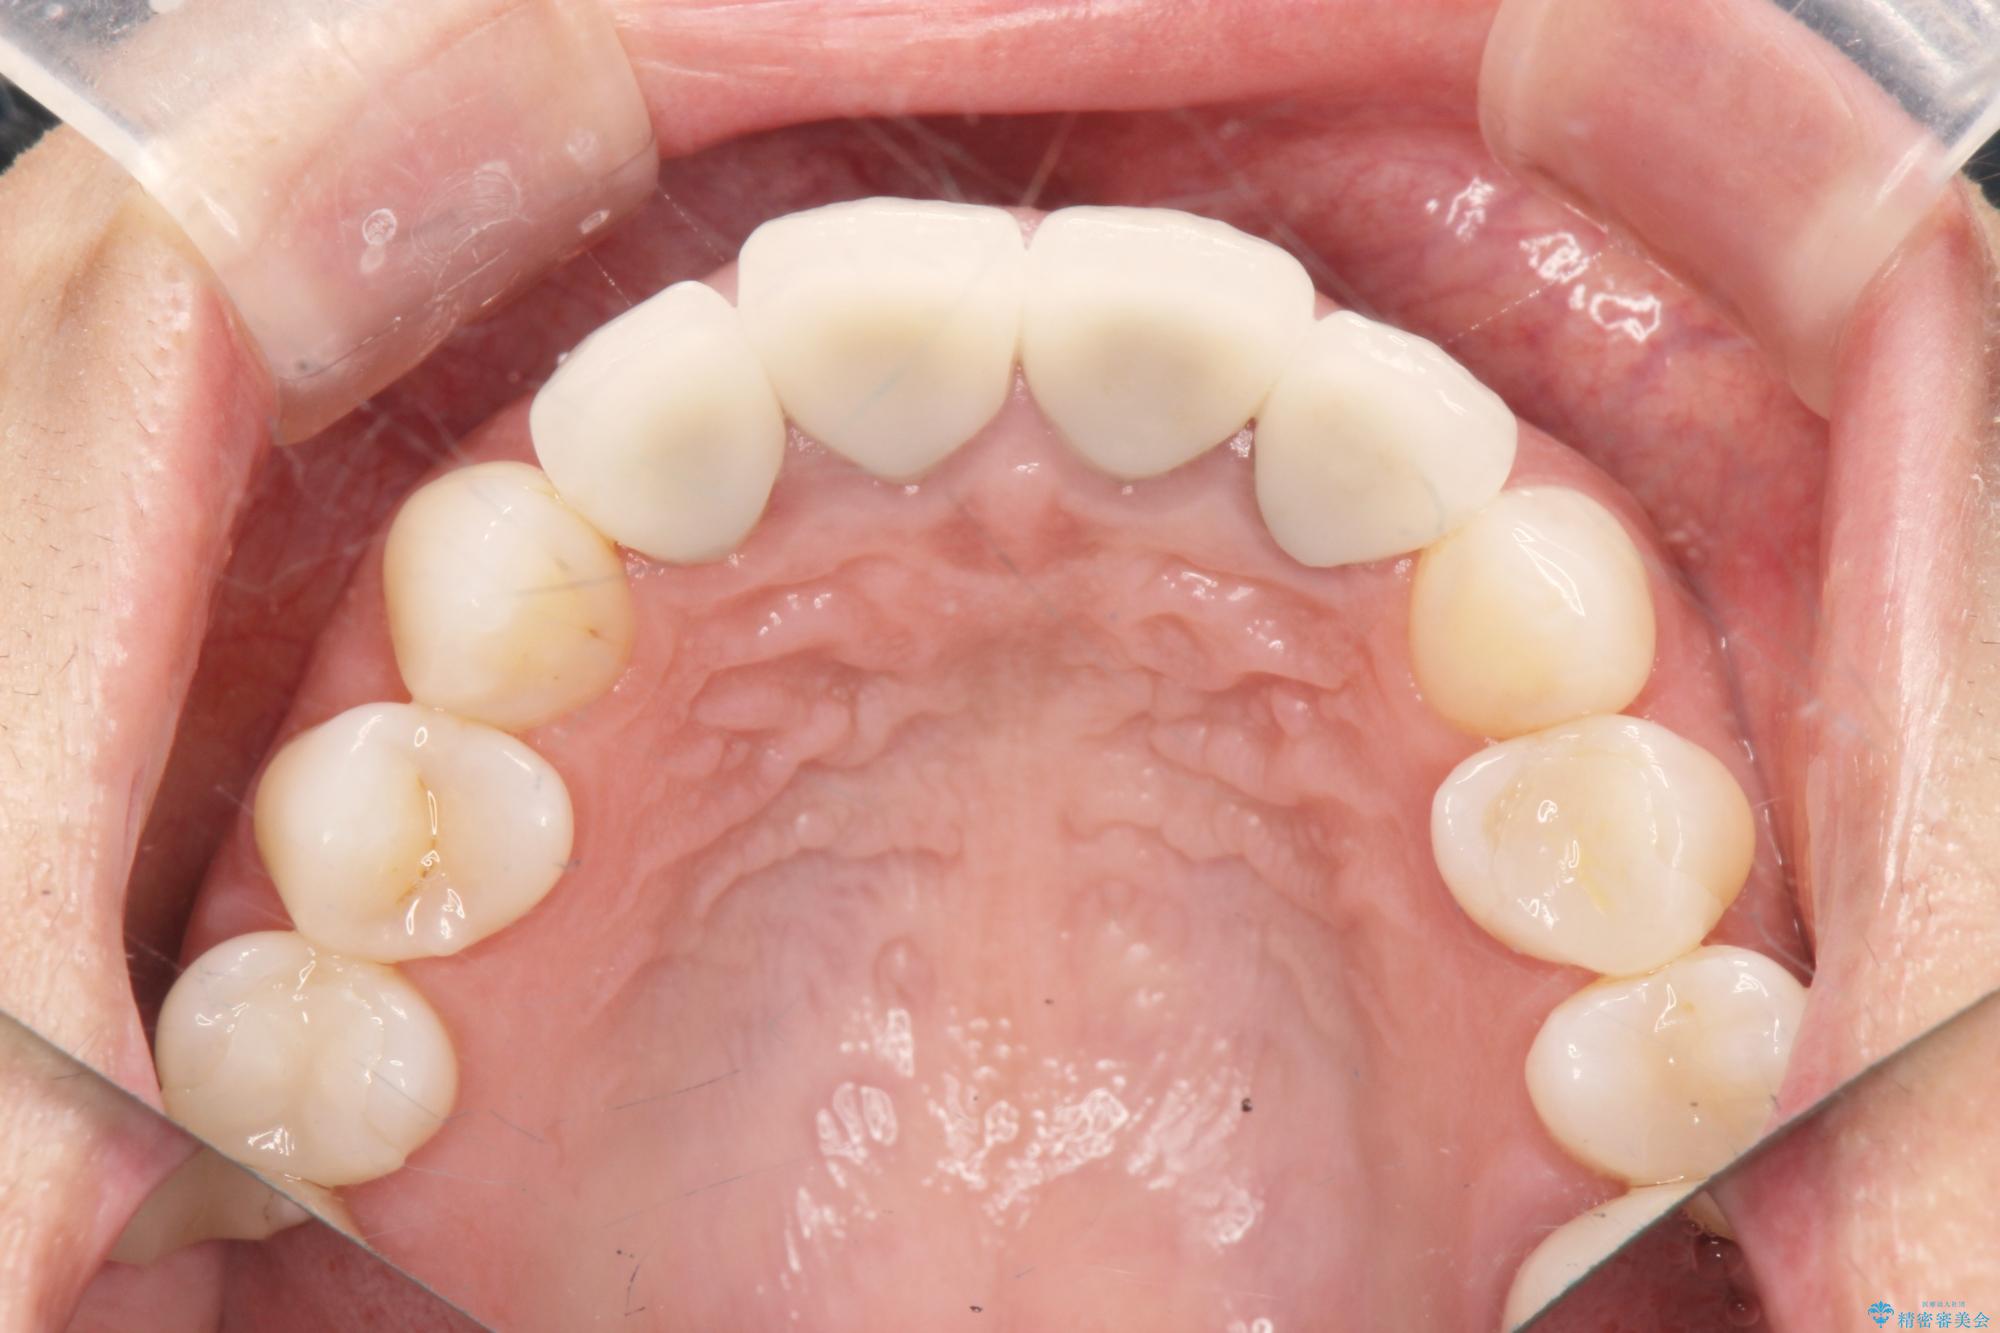

治療後

歯槽堤保存術を併用したブリッジ治療 治療後画像 歯槽堤保存術を併用したブリッジ治療 治療後画像 歯槽堤保存術を併用したブリッジ治療 治療後画像 歯槽堤保存術を併用したブリッジ治療 治療後画像 歯槽堤保存術を併用したブリッジ治療 治療後画像 歯槽堤保存術を併用したブリッジ治療 治療後画像 歯槽堤保存術を併用したブリッジ治療 治療後画像